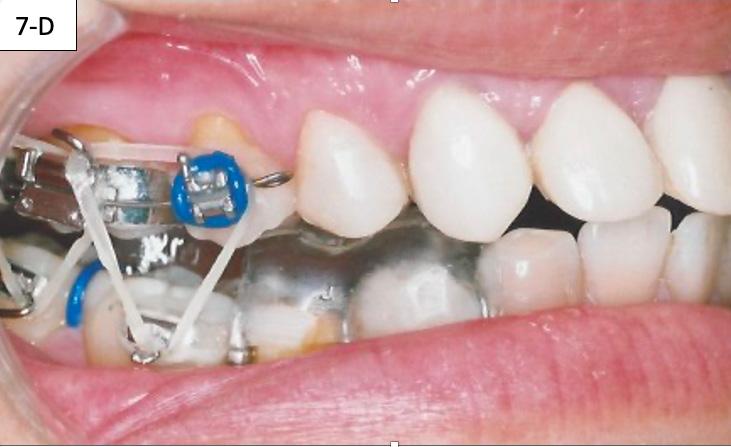

After the patient became accustomed wearing the splint, the acrylic was cut off distally to #46(30) and #36(19). A band was cemented on #17(2), #16(3) and #27(15), #26(14) and brackets/ tubes were bonded on #15(4), #25(13), #37(18), and #47(31). A 016 SS sectional wire was inserted in the maxilla bilaterally from the second molar to the second bicuspid and a ¼” - 4.5 oz elastics were placed for forced eruption of the mandibular second molars (Figure 7-A, B).

When the mandibular second molars became in contact with the maxillary molars, the acrylic was hollowed out from the intaglio of the splint above #46(30) and #36(19). Two ¼” –4.5 oz triangular elastics were placed for forced eruption of the mandibular first and second molars (Figure 7-C, D).

FIG. 7A: Forced eruption of #47(31)

FIG. 7B: Forced eruption of #37(18)